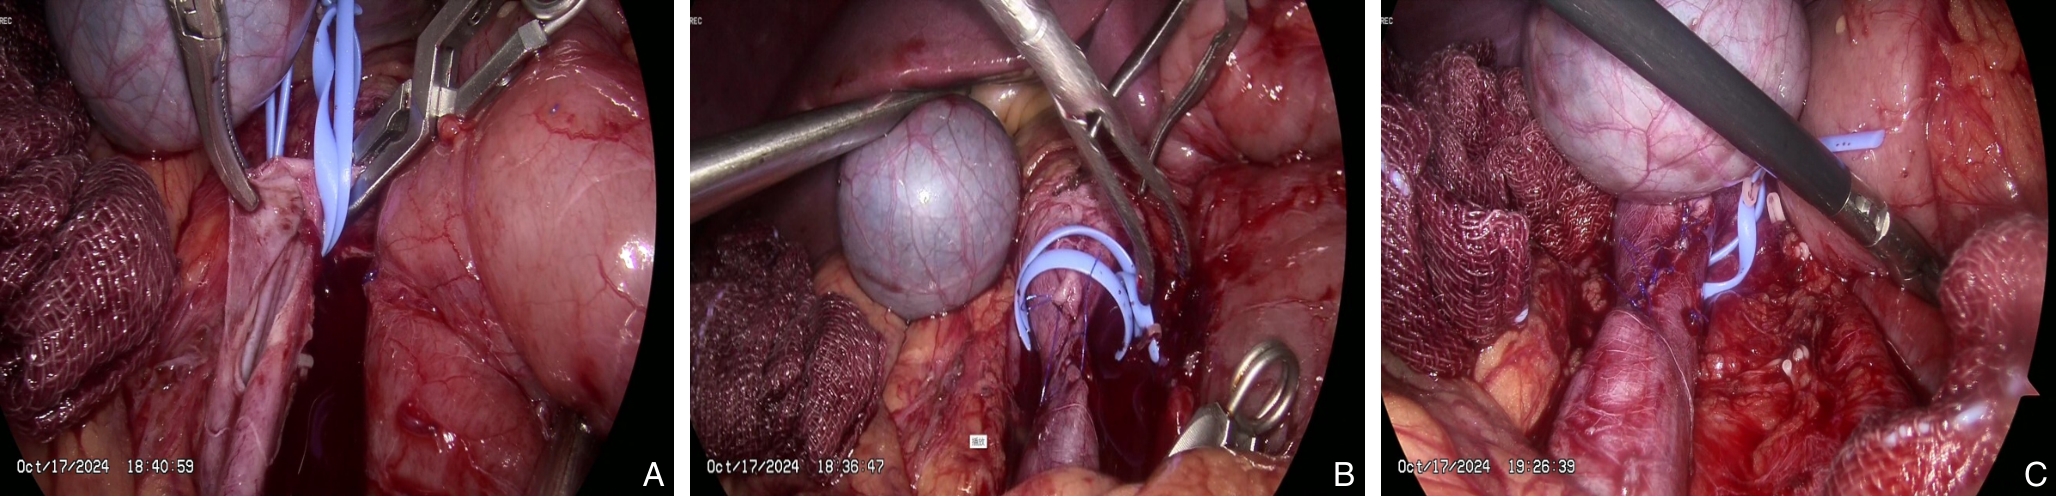

陈松伟,谭海峰,林少芒,张智辉,萧剑彬,李阳勇,蒋小峰,温子龙,艾文佳,李强,曹华燕

2025, 34(12):2710-2716. doi: 10.7659/j.issn.1005-6947.250520

摘要:背景与目的 下腔静脉滤器在预防深静脉血栓脱落导致肺栓塞中具有重要作用,但部分滤器因回收钩贴壁、内膜增生包裹或穿出血管壁等原因,无法经血管腔内途径取出。本研究旨在总结腹腔镜下取出下腔静脉困难滤器的手术经验,评价其安全性与可行性。方法 回顾性分析2024年3月—2025年5月在广州医科大学附属第二医院行腹腔镜下腔静脉滤器取出的12例困难滤器患者临床资料。所有患者均曾尝试经血管腔内途径取出滤器失败。根据滤器位置选择头侧或尾侧入路,经腹腔前正中途径行腹腔镜手术,记录手术成功率、手术时间、术中出血量、围术期并发症及随访情况。结果 12例患者中,伞形滤器10例,梭形滤器2例;滤器植入中位时间为3(1.3~11.5)个月。滤器主要位于肾静脉周围区域(91.7%)。11例采用头侧入路,1例采用尾侧入路。11例(91.7%)成功经腹腔镜完整取出滤器,1例因梭形滤器顶端进入肾区、血管阻断不完全致术中出血失控而中转开腹。平均手术时间为(252.8±83.2)min,中位术中出血量150(50~500)mL。所有患者术后均顺利康复出院,无腹腔或切口感染。随访(9.8±3.8)个月,未见下腔静脉血栓形成或管腔狭窄。结论 对于经血管腔内途径取出失败的下腔静脉困难滤器,腹腔镜下取出术是一种安全、有效的微创替代方案。该术式的成功依赖于合理选择手术入路、充分的滤器段血管阻断及针对不同滤器类型采取个体化取出策略,但对术者腹腔镜血管外科技术要求较高。